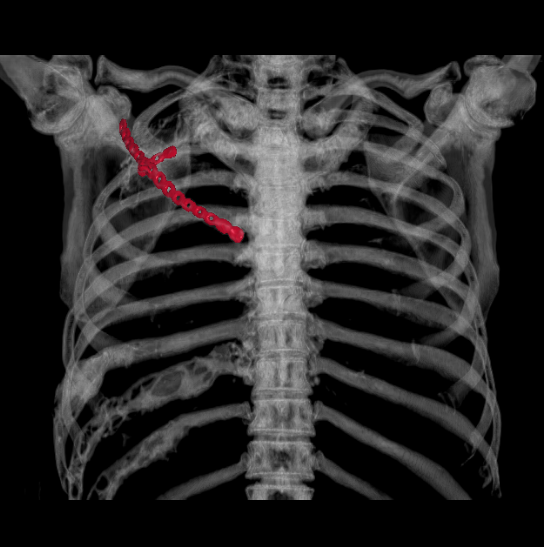

近日,重慶醫(yī)科大學(xué)附屬璧山醫(yī)院(重慶市璧山區(qū)人民醫(yī)院)胸心血管外科為患者實(shí)施全院首例胸壁腫物切除+胸壁重建術(shù),成功為患者去除病灶,目前患者已康復(fù)出院。

榮騰浩副主任醫(yī)師、楊富瑜主治醫(yī)師經(jīng)過全面檢查,研究病例后認(rèn)為:巨大腫物切除后,胸壁“軟化”為常見并發(fā)癥,進(jìn)而導(dǎo)致反常呼吸,影響心肺功能,而患者為體力勞動(dòng)者并且是家庭經(jīng)濟(jì)支柱,“重建”胸廓可使患者恢復(fù)勞動(dòng)能力。胸心血管外科團(tuán)隊(duì)制定完善手術(shù)計(jì)劃后,決定手術(shù)切除后予以Matrix -RIB板重建,手術(shù)過程順利,術(shù)后無(wú)并發(fā)癥,目前患者已康復(fù)出院。